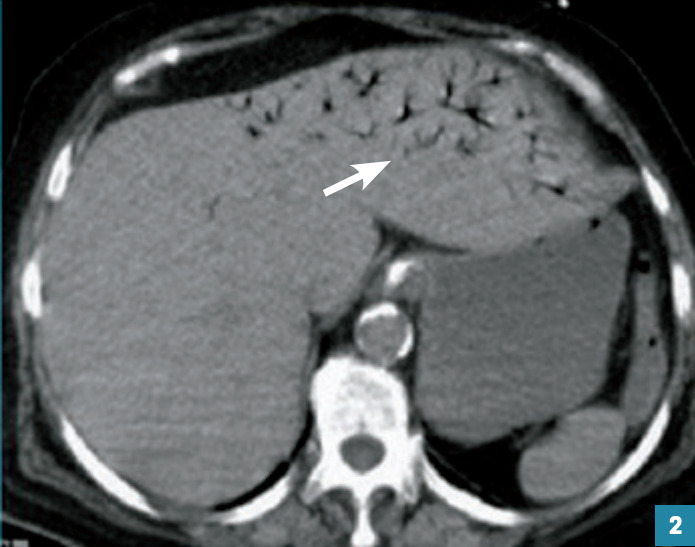

Les signes radiologiques de mauvais pronostic sont un défaut de rehaussement des parois digestives (vascularisation anormale), un épaississement pariétal (dû à la congestion) ou au contraire un amincissement de la paroi nécrosée et parfois une pneumatose pariétale (kystes gazeux dans la paroi intestinale), voire une aéroportie (fig. 2 ).

Les signes radiologiques de mauvais pronostic sont un défaut de rehaussement des parois digestives (vascularisation anormale), un épaississement pariétal (dû à la congestion) ou au contraire un amincissement de la paroi nécrosée et parfois une pneumatose pariétale (kystes gazeux dans la paroi intestinale), voire une aéroportie (